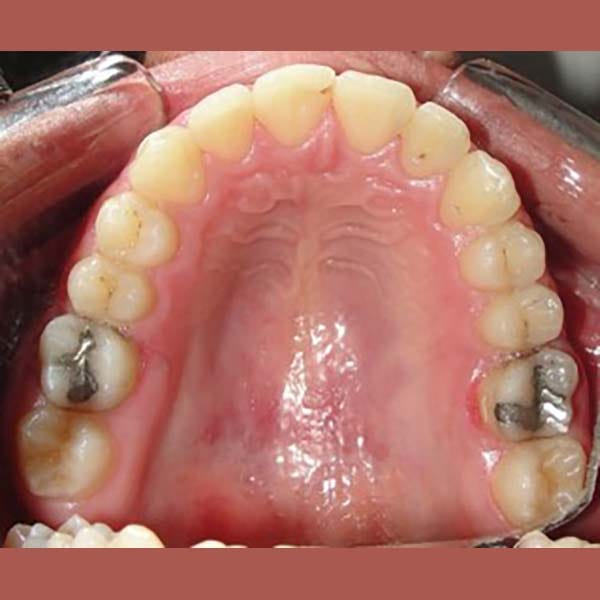

This young man visited me due to the severe protrusion in his teeth. Upon examination, I noticed the presence of molars with large fillings, which are not expected to endure for a long time.

So we decided to extract these two molars and use their space to return the front teeth back, in the end, our friend regained his beautiful smile again.